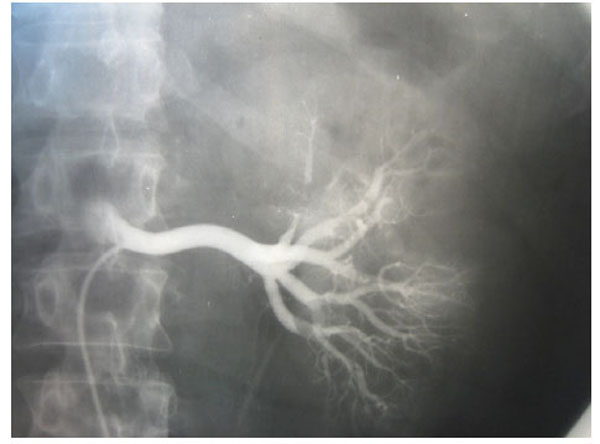

Fig. (3), Fig. (4), Fig. (5), Fig. (6), show images before and after systemic fibrinolytic treatment of two different patients, one suffering from partial emboli occlusion of main renal artery and the other, multiple segmentary intrarenal emboli.

Fig. (4).

Total emboli lysis after 24 hours of systemic fibrinolytic treatment.